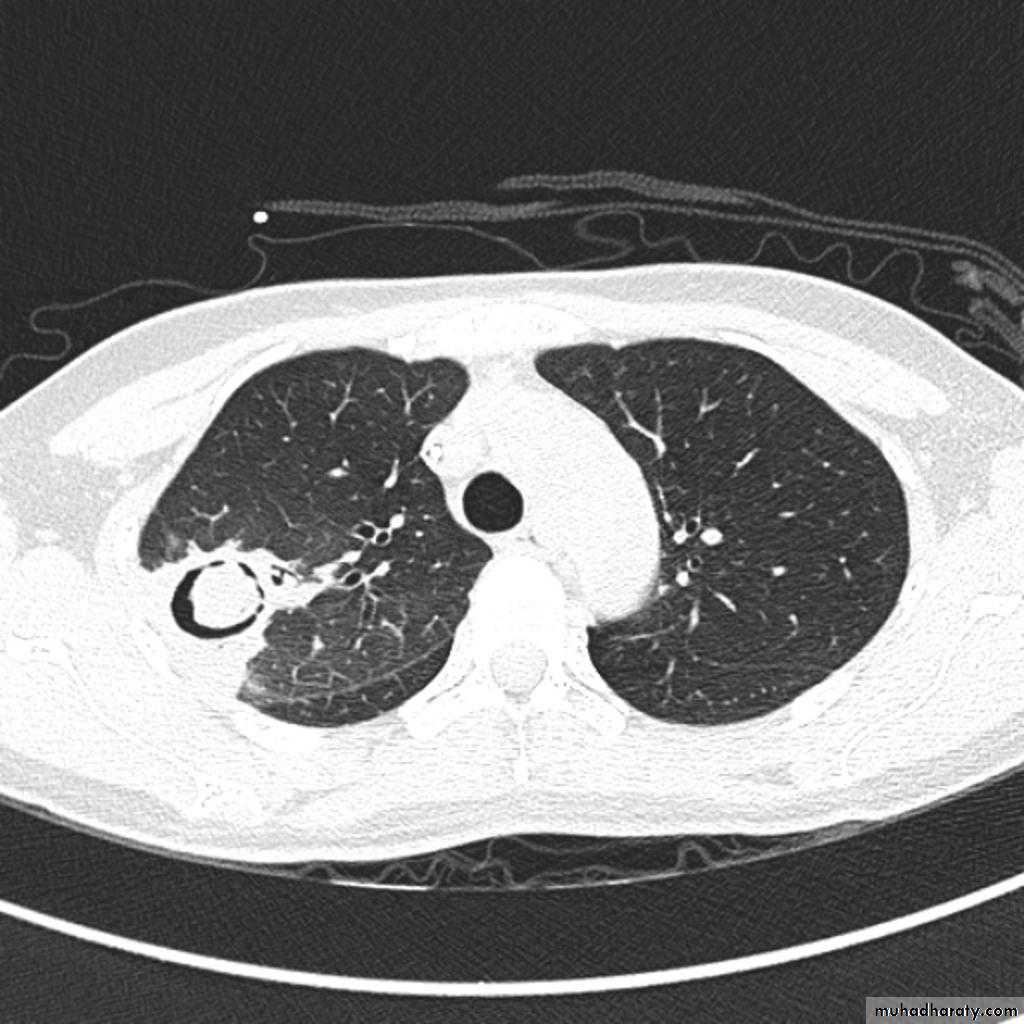

TB abscess

1.patchy consolidation or poorly defined linear and nodular opacities in both apices , upper zone in one lung , & lower zone in other lung ( ulternating lesion ) .2. Post-primary infections are far more likely to cavitate with multiple abscess formation & air fluid level more develop in the posterior segments of the upper lobes.

Recognized complications include:1.colonisation of cavities by fungus, e.g. HYPERLINK "http://radiopaedia.org/articles/aspergilloma" aspergilloma